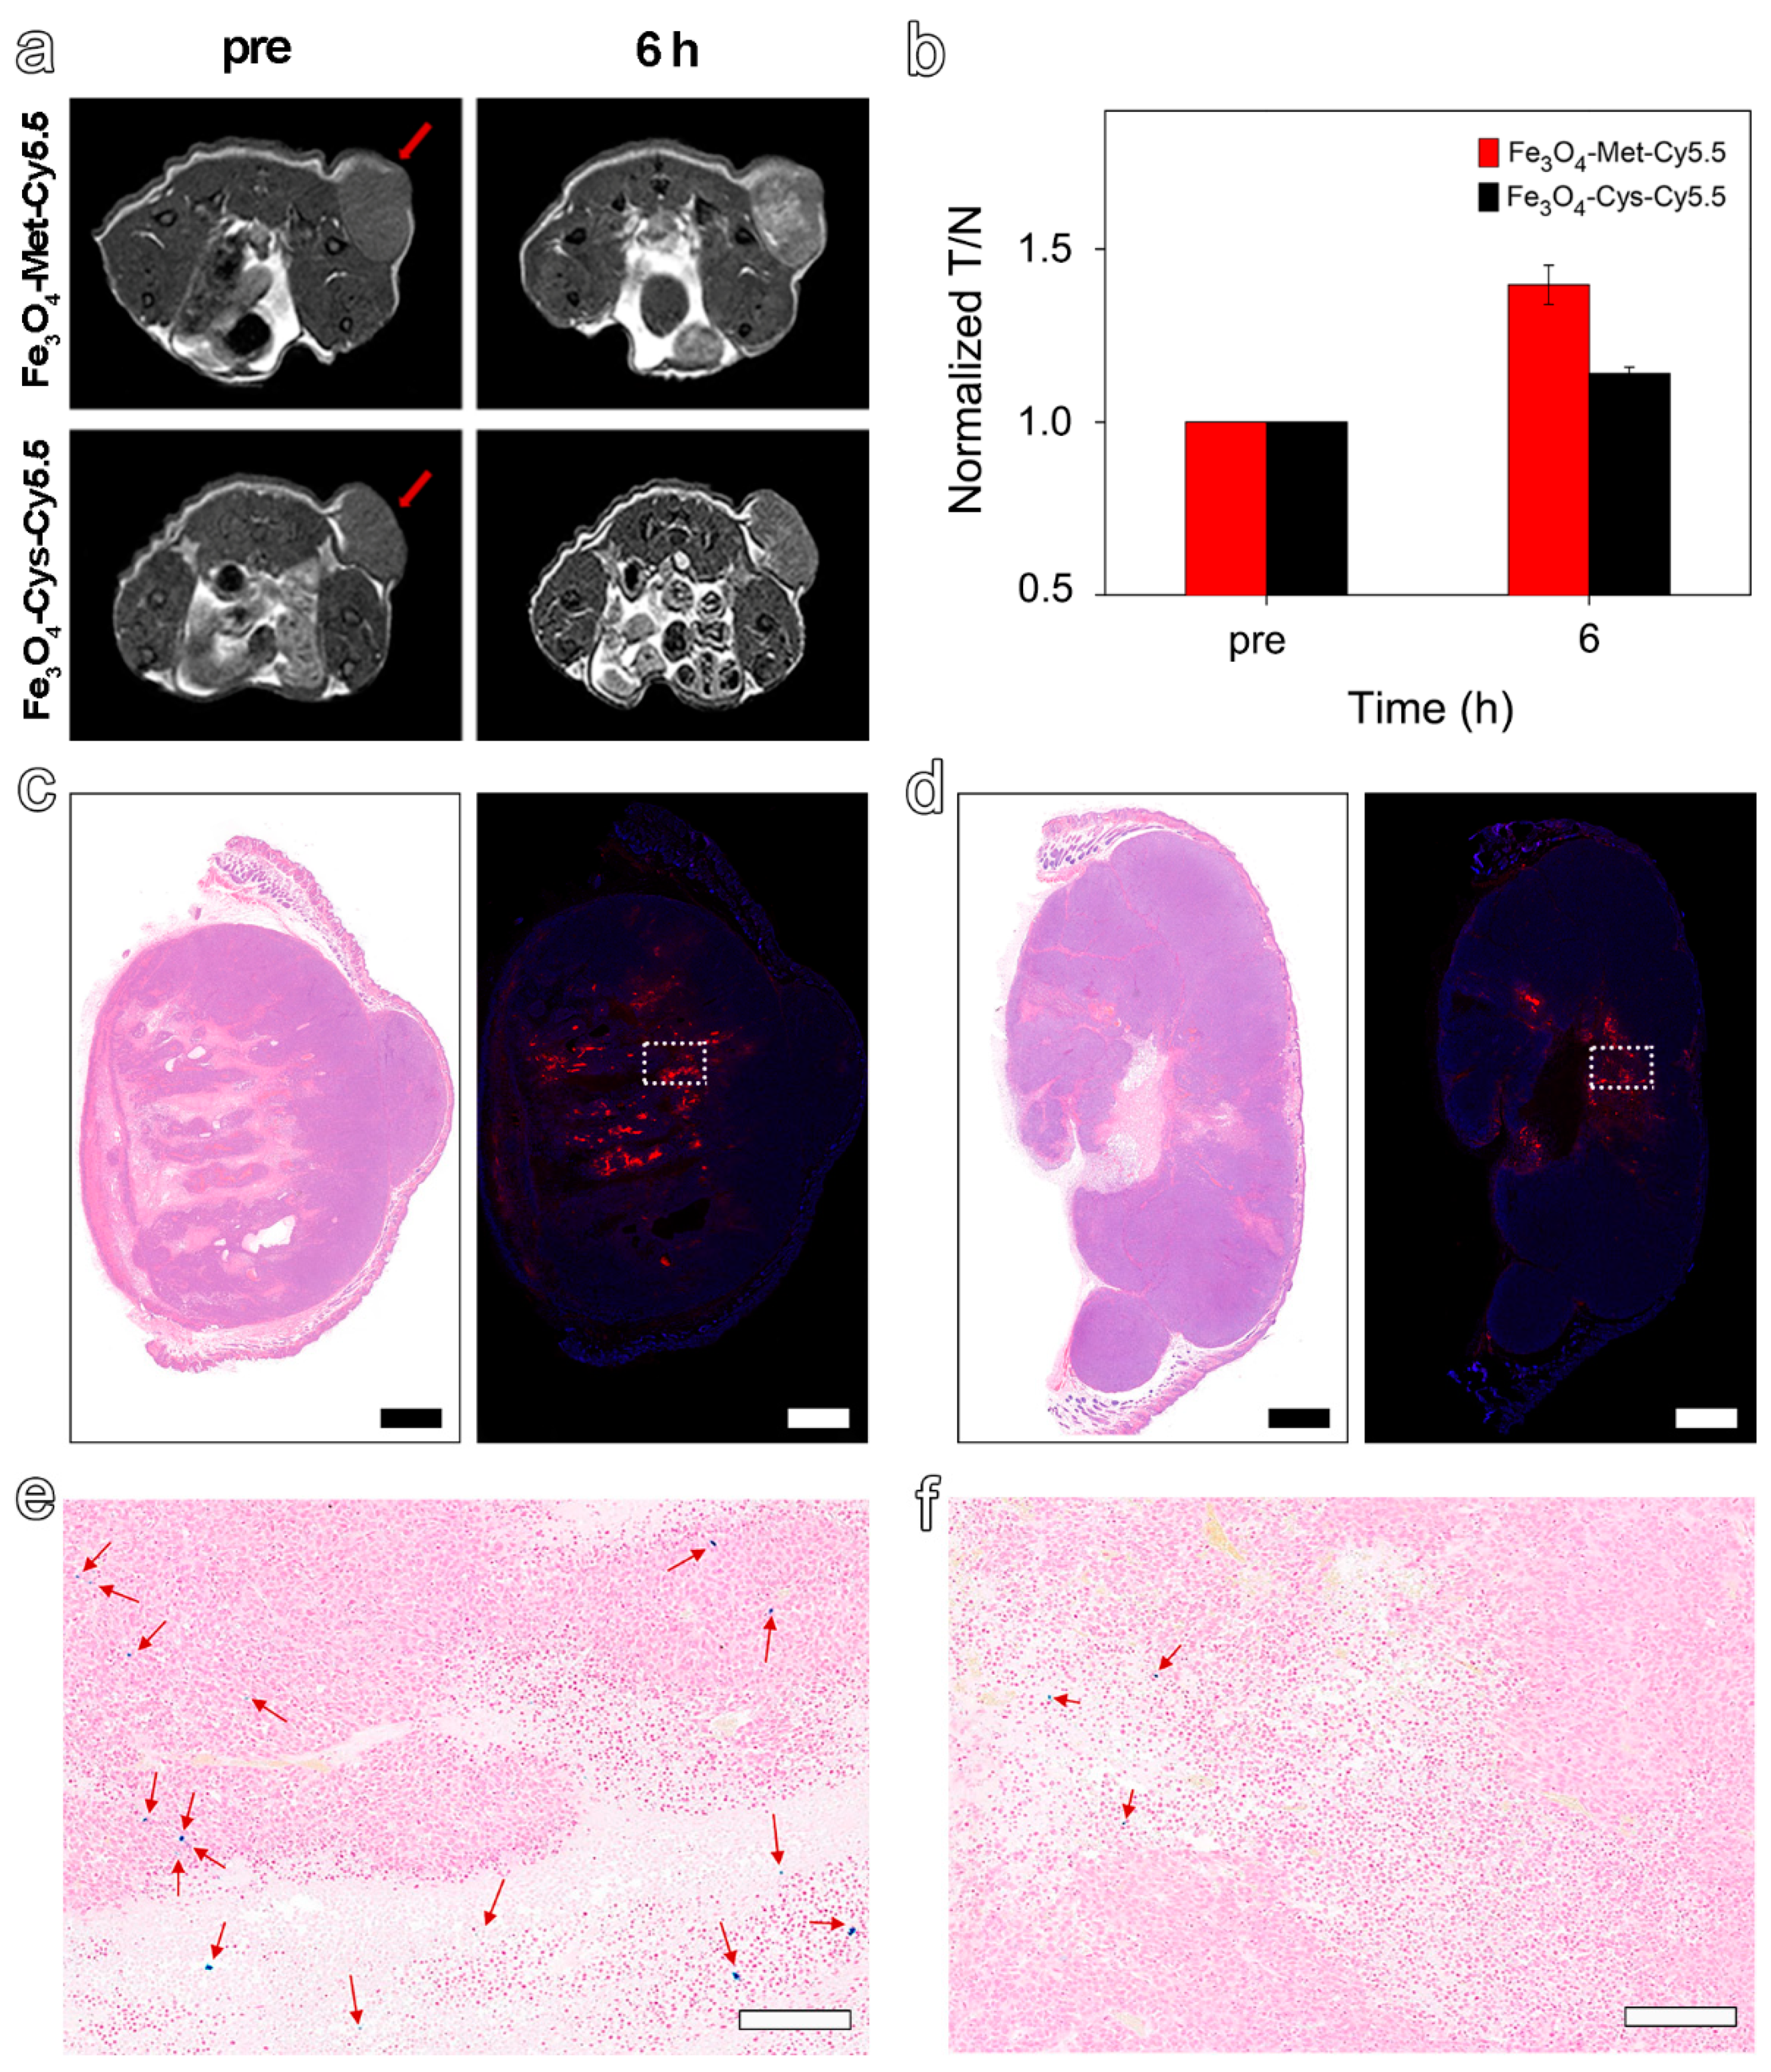

3.4. In Vivo T1-Weighted MRI of Tumors